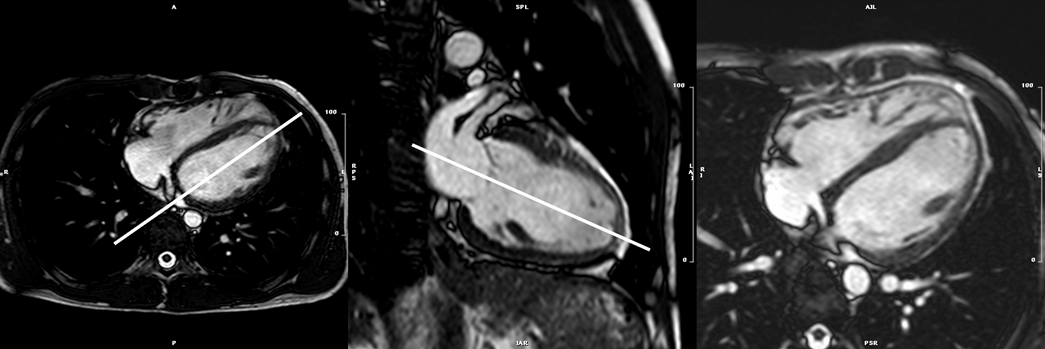

3. bSSFP左室短軸像シネMRI(Fig. 3

1. 左室二腔(垂直)長軸像:体軸横断上で僧帽弁の中心と心部を結ぶスライス(Fig. 4

2. 四腔(水平)長軸像:二腔長軸像に垂直で,僧帽弁と左房の中心を通り,左室の長軸へと続くスライス(Fig. 4

Pediatric Cardiology and Cardiac Surgery 40(4): 260-271 (2024)

Fig. 3 Top: Planning of the short axis image plane parallel to the mitral valve in the 4 chamber long axis plane (left) and 2 chamber long-axis plane (right). Bottom: 18 short axis cine slices shown from base (top left) to apex (bottom right).

Fig. 4 Left: White blood axial scout image through the base of the left ventricle (LV) and right ventricle (RV). Planning of the 2 chamber long axis is shown by the white line. Center: White blood 2 chamber long axis scout image. Planning of the 4 chamber long-axis is shown by the white line. Right: White blood 4-chamber long axis scout image.

Fig. 5 Left: 4-chamber long axis cine image. Center: 2-chamber long axis cine image. Right: 3-chamber long axis cine image.